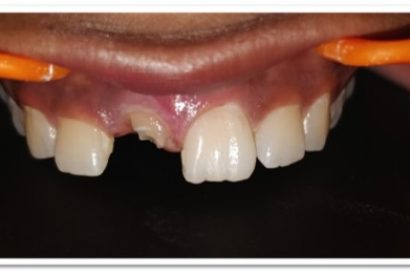

Patient Name:Saba Memon

Tooth Involved :11 , 21

Diagnosis : Ellis Class II Fracture

Treatment : Direct Composite Restoration Using Nanohybrid Composite

Before

After